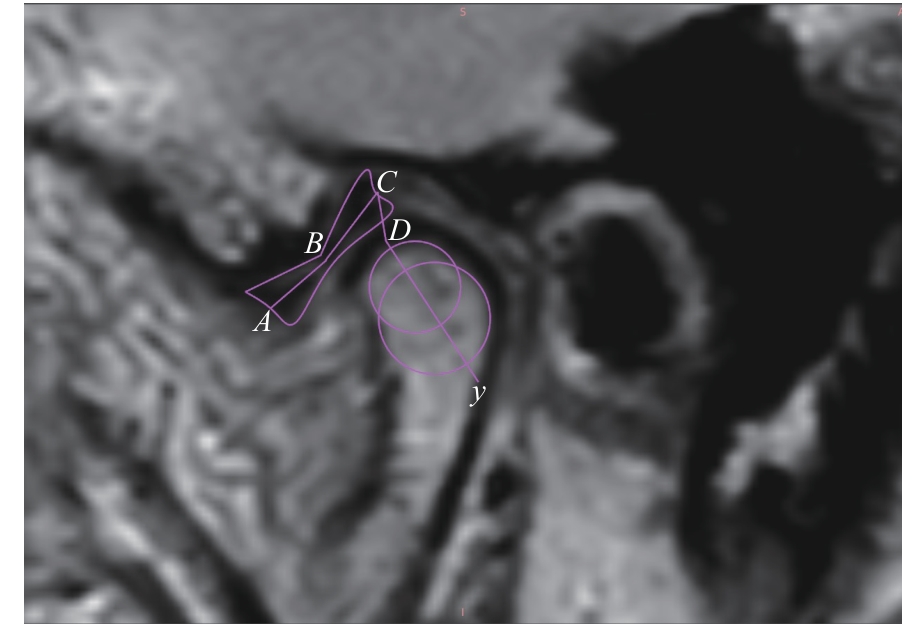

ARAYASANTIPARB R, TSUCHIMOCHI M. Quantification of disc displacement in internal derangement of the temporomandibular joint using magnetic resonance imaging[J]. Odontology, 2010, 98(1): 73-81.

|

| [20] |

YANG Z J, WANG M G, MA Y W, et al. Magnetic resonance imaging (MRI) evaluation for anterior disc displacement of the temporomandibular joint[J]. Med Sci Monit, 2017, 23: 712-718.

ZHANG Q, YE Z, WU Y G, et al. Nonlinear relationship between temporomandibular joint disc displacement distance and disc length: a magnetic resonance imaging analysis[J]. J Clin Med, 2022, 11(23): 7160.